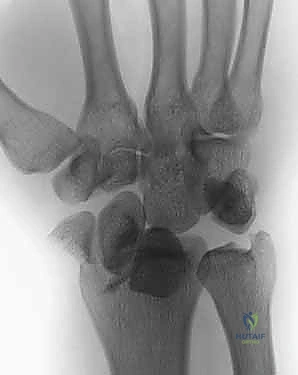

- الأشعة السينية (X-rays):

هي الخطوة الأولى لتقييم الكسر. يتم أخذ صور من زوايا متعددة (أمامية خلفية، جانبية، ومائلة) لتحديد موقع الكسر الأساسي ودرجة الانزياح والتقصير في عظم الكعبرة.

- التصوير المقطعي المحوسب (CT Scan) مع إعادة البناء ثلاثي الأبعاد:

هذا هو المعيار الذهبي الذي يعتمده الدكتور هطيف لجميع كسور المفصل المعقدة. تتيح الأشعة المقطعية رؤية كل شظية عظمية بوضوح تام، وتحديد حجمها، وموقعها، ودرجة تفتت السطح المفصلي بدقة ملليمترية. من خلال إعادة البناء ثلاثي الأبعاد (3D Reconstruction)، يمكن للدكتور هطيف "رؤية" الكسر من جميع الزوايا قبل فتح الجلد، مما يسمح له باختيار الغرسات (الصفائح والمسامير) الدقيقة لكل شظية وتحديد المداخل الجراحية المثلى.